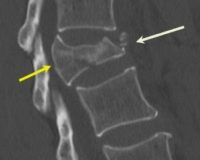

• Рентген позвоночника. Наиболее информативным является боковой снимок, на котором индекс клина рассчитывается по специальной формуле (высота вентрального края, деленная на высоту дорсального края позвонка). Показатель ниже 0,92 считается признаком сжатия. Другими признаками перелома являются потеря структурной модели, увеличение интенсивности теней и вмятины на концевых пластинах.

• КТ и МРТ. Из-за малых значений измерения определение индекса клиновидности является достаточно субъективным критерием, особенно при незначительном сжатии. Для уточнения результатов рентгенографии по показаниям назначают компьютер или МРТ позвоночника. Методики позволяют создать трехмерное изображение пораженного участка, детально изучить структуры твердых и мягких тканей.